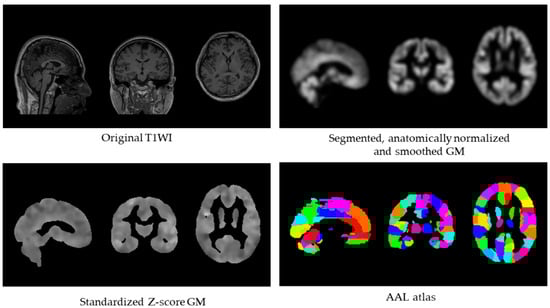

Figure 1 illustrates the computational pipeline used to derive the GM-BHQ metric.

Figure 1. GM-BHQ calculation pipeline. Processing steps from original T1-weighted image (top left) to segmented, normalized, and smoothed gray matter (top right), standardized Z-score image (bottom left), and regional extraction using the AAL atlas with 116 regions (bottom right). The GM-BHQ is computed as the average of regional quotient values.